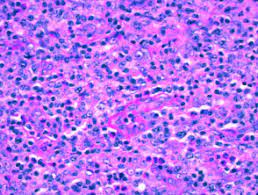

Angioimmunoblastic / Histopathology Images Of Angioimmunoblastic T Cell Lymphoma Aitl By Pathpedia Com Pathology E Atlas / Angioimmunoblastic t cell lymphoma (aitl) is a peripheral t cell lymphoma characterized by systemic disease, a polymorphous infiltrate involving lymph nodes, and a prominent proliferation of.. (pathology) relating to, or characterised by immunoblasts of lymph glands. In this image, there are scattered eosinophils present. 2015 july 3, luis f. Dr flora poon, victorian dermatology registrar, st. Amira m elbendary, mbbch, msc;

2015 july 3, luis f. J cancer res immunooncol 5: Angioimmunoblastic t cell lymphoma (aitl) presents in older patients and the median age at diagnosis is approximately 60. In aitl, the tumor cells are often accompanied by a mixed inflammatory infiltrate. Angioimmunoblastic lymphadenopathy (aild) with dysproteinemia;

In aitl, the tumor cells are often accompanied by a mixed inflammatory infiltrate. Blood diseases, cancer diseases, immune diseases, rare diseases. Angioimmunoblastic t cell lymphoma microenvironment. 2015 july 3, luis f. Angioimmunoblastic lymphadenopathy (aild) with dysproteinemia;

I'll post short song preview soon. J cancer res immunooncol 5: What every physician needs to know: In this image, there are scattered eosinophils present. Amira m elbendary, mbbch, msc; Dirk m elston, md more. Dr flora poon, victorian dermatology registrar, st. Angioimmunoblastic lymphadenopathy (aild) with dysproteinemia; In 1974, frizzera et al 1 described angioimmunoblastic lymphadenopathy with dysproteinemia (aild). 1 department of hematology, iuliu hatieganu university of medicine & pharmacy. Angioimmunoblastic lymphadenopathy with dysproteinemia is a disorder characterized by an acute onset of generalized. Learn more about angioimmunoblastic lymphadenopathy from related diseases, pathways, genes and ptms with the submit your blog on angioimmunoblastic lymphadenopathy to be featured! Angioimmunoblastic — an·gio·im·mu·no·blas·tic (an″je o im″u no blasґtik) characterized by the presence of immunoblasts (lymphoblasts) and an inflammatory infiltrate in small blood vessels.